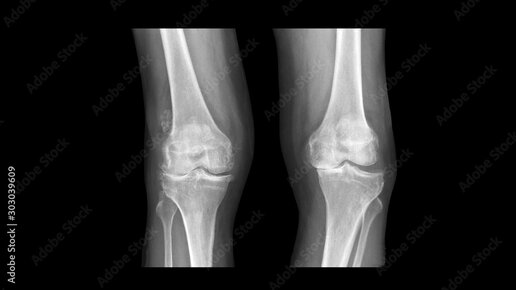

Всем добрый день! В сегодняшней статье расскажу о методике рентгенографии костей и крупных суставов (коленных, тазобедренных, плечевых, локтевых, голеностопных, лучезапястных). Не буду затрагивать рентгенографию стоп и кистей — на эти темы будут отдельные статьи, не пропустите! Отвечу на вопросы: ❓ Что это за исследование?

❓ Какие недостатки? Рентгенография костей и суставов — доступный метод лучевой диагностики заболеваний и травматических повреждений этих структур...